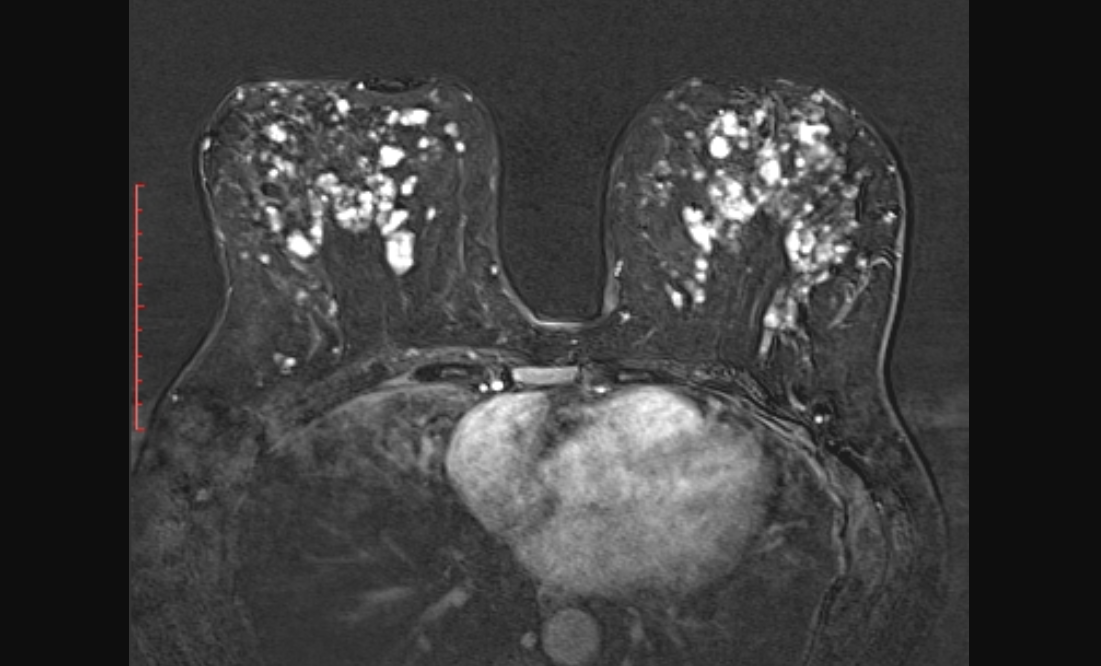

Многочисленные кисты обеих молочных желез.